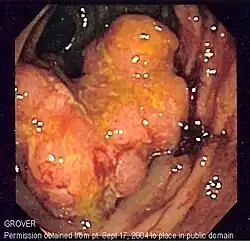

Em 85% dos casos, o cancro colorretal é precedido por uma lesão benigna conhecida por pólipo. Dependendo da característica deste pólipo, ele pode se tornar maligno e iniciar o cancro. Devido a este processo é que se faz a prevenção deste tipo de tumor com a colonoscopia, já que este exame permite o diagnóstico e a retirada do pólipo. Nos outros 15% dos casos, o tumor ocorre devido a uma doença genética, e se caracteriza por acometer pacientes mais jovens e por não apresentar o pólipo como lesão pré-maligna, ou seja, surge diretamente na parede do intestino.

O tipo do tumor é geralmente diagnosticado através da análise de tecido removido através de uma biópsia ou cirurgia. O diagnóstico patológico geralmente contém a descrição histológica do cancro, e o grau. O tipo mais comum de cancro colorretal é adenocarcinoma, que compõe 95% dos casos - acredita-se que a maioria dos casos de cancro colorretal envolvam tumores originários de pólipos adematosos. Outros tipos, mais raros, de cancro colorretal, incluem linfoma e carcinoma espinocelular. As causas do cancro colorretal não são conhecidas com exatidão no presente.

Adenocarcinoma é um tipo de tumor maligno epitelial, que se origina do epitélio glandular da mucosa colorretal. Tal tumor invade a parede, infiltrando a mucosa muscular, a submucosa, e daí, a muscularis propria. As células do tumor abrigam estruturas tubulares irregulares, de estrutura pluristratificada, lúmens múltiplos, e estromas reduzidos. Por vezes, as células do tumor secretam muco, que invade o fluido intersticial, produzindo grandes agrupamentos de muco e colóide (que, visualmente, aparecem como "espaços vazios") - é o chamado adenocarcinoma colóide, pouco diferenciado. Se o muco permanece dentro da célula do tumor, o muco empurra o núcleo celular para a periferia da célula - célula do tipo signet-ring. Dependendo da arquitetura glaudular, pleomorfismo celular, e padrão da secreção de muco, o adenocarcinoma pode ser categorizado em três graus de diferenciação: bem diferenciado, moderadamente diferenciado, e mal diferenciado.[48]